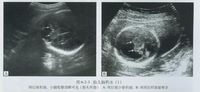

1、无脑儿:是先天畸形中最常见的一种,是神经管缺陷中最严重的一种,女胎比男胎多4倍,呈“哇样”面容,颈项短,无大脑,仅见颅底或颅底部分组织,不可能存活。脊柱裂:属脊椎管部分未完全闭合的状态,也是神经管畸形中最常见的一种。多发生在胸腰段。分为脊椎管缺损,为隐形脊柱裂;两个脊椎骨缺损,为脊髓脊膜膨出;形成脊髓部分的神经管缺失,称为脊髓裂,同时合并脊柱裂。隐形产前B超难发现,较大的脊柱裂产前B超较易发现。脑积水:是脑脊液过多的蓄积于脑室,常伴脊柱裂,足内翻等畸形。

2、先天性心脏病:单心房单心室是一种严重的先天性心脏病发育不全,预后不良,一经诊断应建议引产裂:也成为内脏外翻,是一侧腹壁全层缺损所致,B超检查可见胎儿腹腔空虚,胃肠等内脏器官漂浮在羊水中,表面无膜覆盖,腹裂总体预后较好,但伴肝脏突出的,死亡率有所上升。

3、21-三体综合症:也成为唐氏综合症,先天愚型,是染色体异常中最常见的一种,为第21号染色体多一条所致。母亲年龄越大,发生率越高。目前有妊娠早期NT联合血清学筛查,中期血清学筛查及外周血无创性产前筛查。